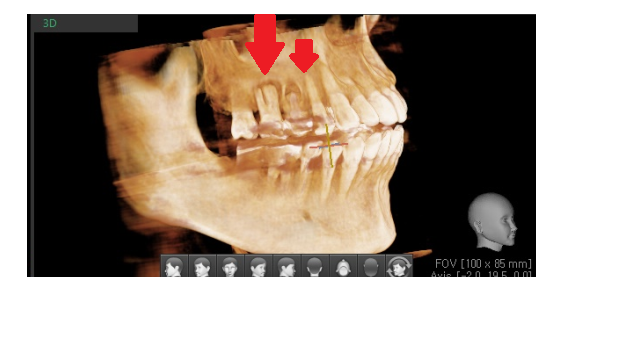

230529

ct에서도 뼈이식한 흔적들이 잘 보입니다.

그렇지만 아직은 부족하여

2달을 더 기다립니다.